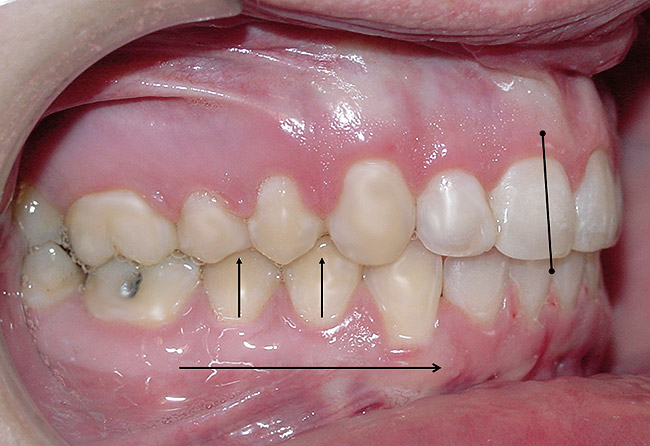

The position, shape, length, and inclination of the maxillary canines will affect the anterior frenal midline position of the mandible. This position may or may not coincide with the midline of the teeth, but gives an indication of the location of the left and right condyles in their fossae. The canines serve as lateral positioners of the mandible. The more lingual the maxillary canine inclination on one side, the more the mandible will shift to the opposite side and the condyle distalize on the opposite side (Figure 6, Figure 7 and Figure 8).

Figure 6  The inclination of the canines provide  the midline position of the mandible. When these  teeth are inclined (eg, the right canine in this  case), they tend to shift the mandible away from  the midline (in this case toward the left).

Figure 6

Figure 7  The left side of the patient shows how  maxillary molars and premolars can cause the  mandibular molars to be lingually inclined as  the teeth come into occlusion.

Figure 8  This case shows the shift of the  mandible from the point of first contact to full  closure because of the anterior restriction, which  has caused the mandible to shift posteriorly and  to the left. This patient experienced symptoms  of right lateral pterygoid tenderness with left  TMJ pain, left-sided headaches, and neck stiffness.  Release of this restriction allowed the  mandible to reposition itself to the midline with  reduction of the symptoms.